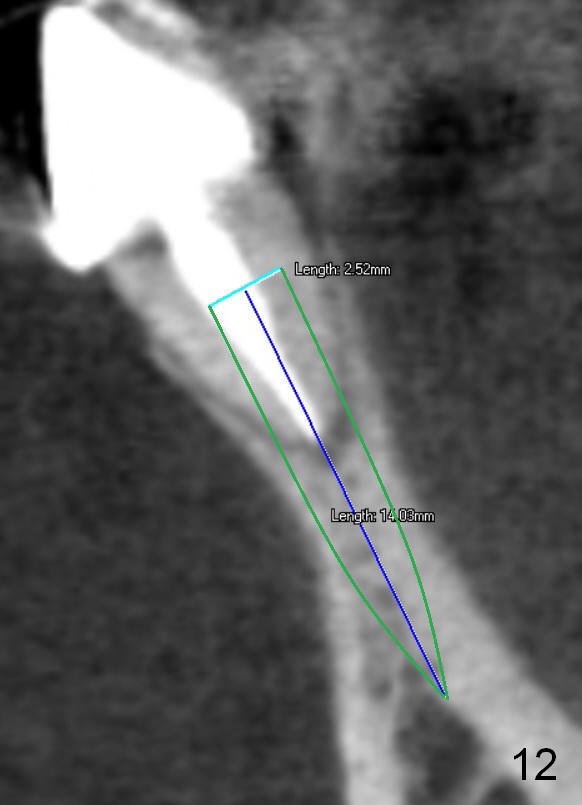

Fig.7 shows these two one piece implants immediately prior to cementation of the FPD (Fig.8). They are much more parallel to each other after prep, as compared to Fig.6. Fig.9 shows apparent bone growth around #24 implant (at the crest) 6,9 months post cementation and surgery, respectively. Orthodontic treatment will incorporate the fixed partial denture. Fig.10 shows that bone grows coronally (arrow) to cover 3 threads (from #6 thread to #3) at the site of #24 one year after functioning. There is mild buccal gingival infection involving #26 retainer. Preop CBCT is reviewed to determine whether it is related to potential thread exposure. It appears that at the sites of #24 (Fig.13,14) and 26 (Fig.11,12), 2.5 mm implant is more appropriate for the narrow ridge than 3.0 mm one. In fact, periimplantitis develops at #26 two years of absence of perio maintenance (because of atrial fibrillation with blood thinner; Fig.15, 3 years 7 months post cementation). Periimplantitis persists 4.5 months later. Although water pik is purchased, it is not used often because of low blowing force. If needed, remove the FPD atraumatically. Unwind the implant, clean the coronal threads with Titanium brush or remove the exposed threads and replant the implant with bone graft.

The infection persists at #26 four years 8 months post cementation (Fig.16 *). CBCT is taken. In fact the implant at #26 was placed lingual (Fig.17), while that at #24 buccal (Fig.20). The 2nd option is to remove the implant at #26 and place a 2 mm one at #25 (Fig.18,19). Fabricate a 3-unit cantilever FPD. Take 5x5 cm CT with 1.2 mm drill in place for 10 mm. Change the trajectory and position if necessary.